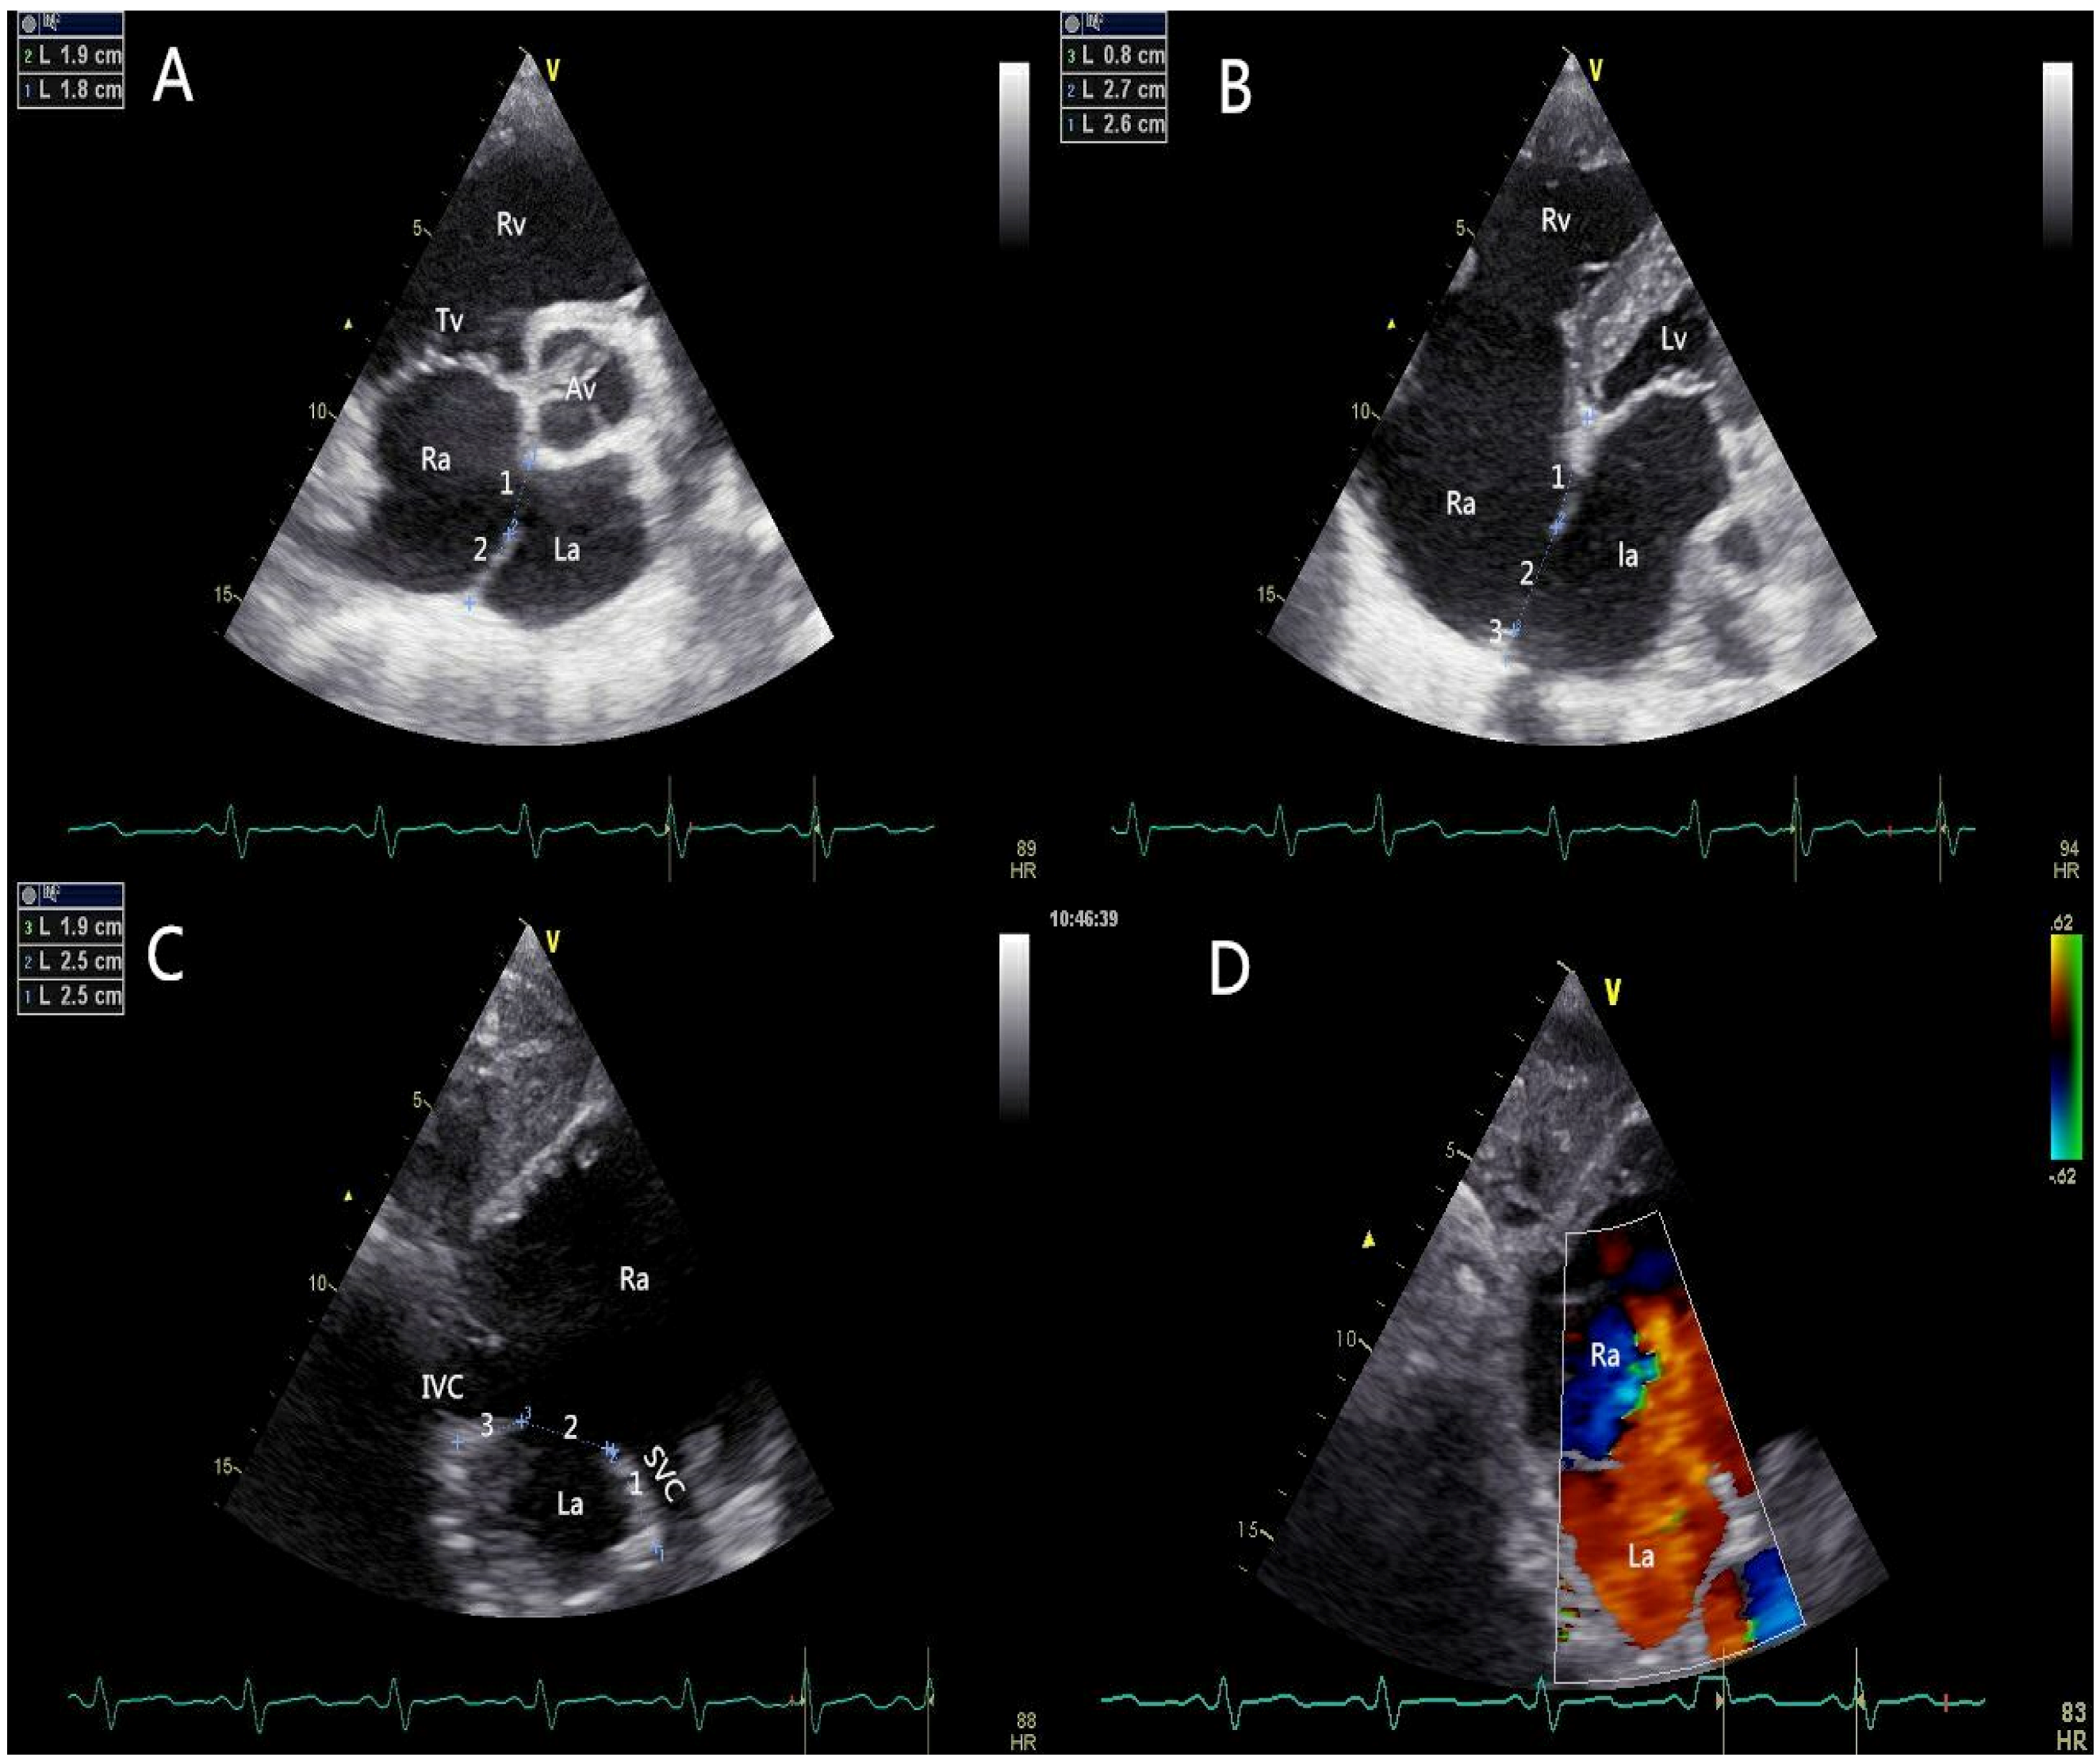

All patients should be evaluated using TTE in terms of defect size, location, rims, adjacent structures, and cardiac function. The edge of the defect was divided into six areas according to their locations or neighboring structures (Figure 2): upper rim (Up-r), atrioventricular valve rim (AVV-r), aortic rim (Ao-r), posterior rim (Po-r), SVC rim (SVC-r), and IVC rim (IVC-r). A floppy septum was considered a normal rim. A “Union Score” was utilized to select patients who were suitable for PAC (Table 1).

Figure 2.

Pre-procedural transthoracic echocardiographic assessment. (A) The short-axis left parasternal view of aortic valve delineated the aortic rim and the posterior rim of the defect; (B) The four-chamber view showed the atrioventricular valve rim and the upper rim; (C) The short axis subcostal view showed the SVC rim and IVC rim; (D) The short axis subcostal view (coloured) showed the blood flow cross the atrial septum (left to right). AV: aortic valve; RA: right atrium; LA: left atrium; RV: right ventricle; LV: left ventricle; TV: tricuspid valve; IVC: inferior vena cava; SVC: superior vena cava.

The figure shows the transthoracic echocardiographic view of ASD without an aortic rim in a 73-year-old patient (Union Score = 0 + 3 + 3 + 2 + 3 + 3 = 14 points). The short-axis left parasternal view of the AV delineated the entire length of the ASD (3A-1), the aortic rim (deficient, 0 points), and the posterior rim (3A-2, 19 mm, 3 points). The four-chamber view shows the atrioventricular valve rim (3B-3, 26 mm, 3 points) and the upper rim (3B-1, 8 mm, 2 points), and the maximum length of the ASD (3B-2) could be observed in this view. The short-axis subcostal view shows the length of the defect (3C-2), the SVC rim (19 mm, 3 points), and the IVC rim (25 mm, 3 points). The figure shows the transthoracic echocardiographic view of the ASD with an adequate SVC rim and an adequate IVC rim. The short-axis subcostal view (colored) shows the blood flow across the atrial septum (left to right) (3D).